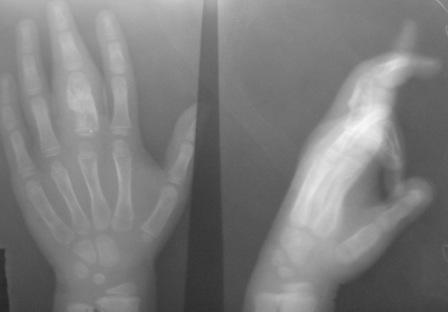

Уважаемые коллеги, на осмотре девочка 2006 г.рожд. Со слов матери 3мес. назад заметила припухлость основного фаланга 3-пальца, которая постепенно увеличилось до настоящего размера где-то в течении месяца, не болит, ребенка не беспокоит, признаки воспаления отсутствуют. Консультация онколога, биопсия - опухоль исключена (со слов матери), фтизиоортопед - тбс исключен. От основной фаланги 3 пальца к головке 4-пястной кости под кожей прощупывается хрящевидная ткань. Р-граммы от 10 декабря и 15 февраля, и фото прилагается. Что делать? Уважаемые коллеги, помогите! С уважением Абдурашид.

Добрый день, уважаемый Абдурашид. Судя по рентгенограмме, к сожалению не очень качественной, речь может идти о варианте дисхондроплазии, которую обозначают, как солитарную хондрому. Рентгенологически они проявляются в 3 вариантах-в виде интрамедуллярно и центрально расположенной энхондромы с вертеннобразным вздутием диафиза изнутри и истончением кортикальной пластинки, в виде опухоли, расположенной эксцентрично с заполнением части кортикального слоя и характерным костным козырьком, в виде экхондром, выступающих за пределы кости

Уважаемый Игорь Владимирович! Я очень рад Вас услышать! И в самом деле это один из вариантов дисхондроплазии ( т.н. болезнь Оллье), так как принесли результат биопсии: -"эмбриональный хрящевой ткань, симулирующий хрящевую опухоль"

Конечно, мы во время операции будем брать материал на гистологию, а также удаление очага и замещение аутотрансплантатом тоже в плане рассматривается, как на примере, которая была представлена на форуме. правда снимки не очень качественные, прощу извинения!